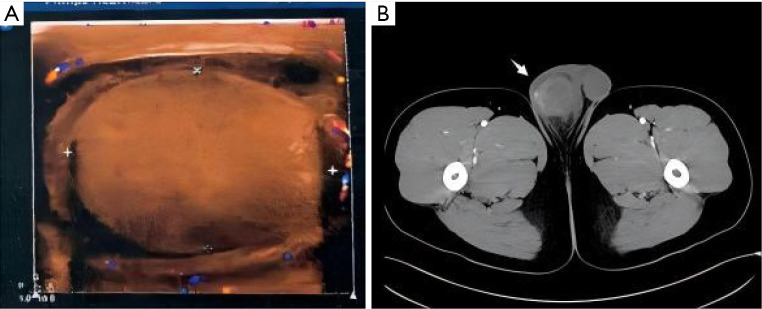

Case description: Clinical information for 11 patients with testicular abscesses who were diagnosed for surgical treatment in our hospital between 2006 and 2023 was retrospectively examined. Out of the eleven patients with nontuberculous testicular abscesses who had postoperative testicular pathology confirm the diagnosis, five had imaging-diagnosed testicular infarcts, two received orchiectomy due to misdiagnosis of testicular tumors, and one had an incorrect diagnosis of testicular torsion.